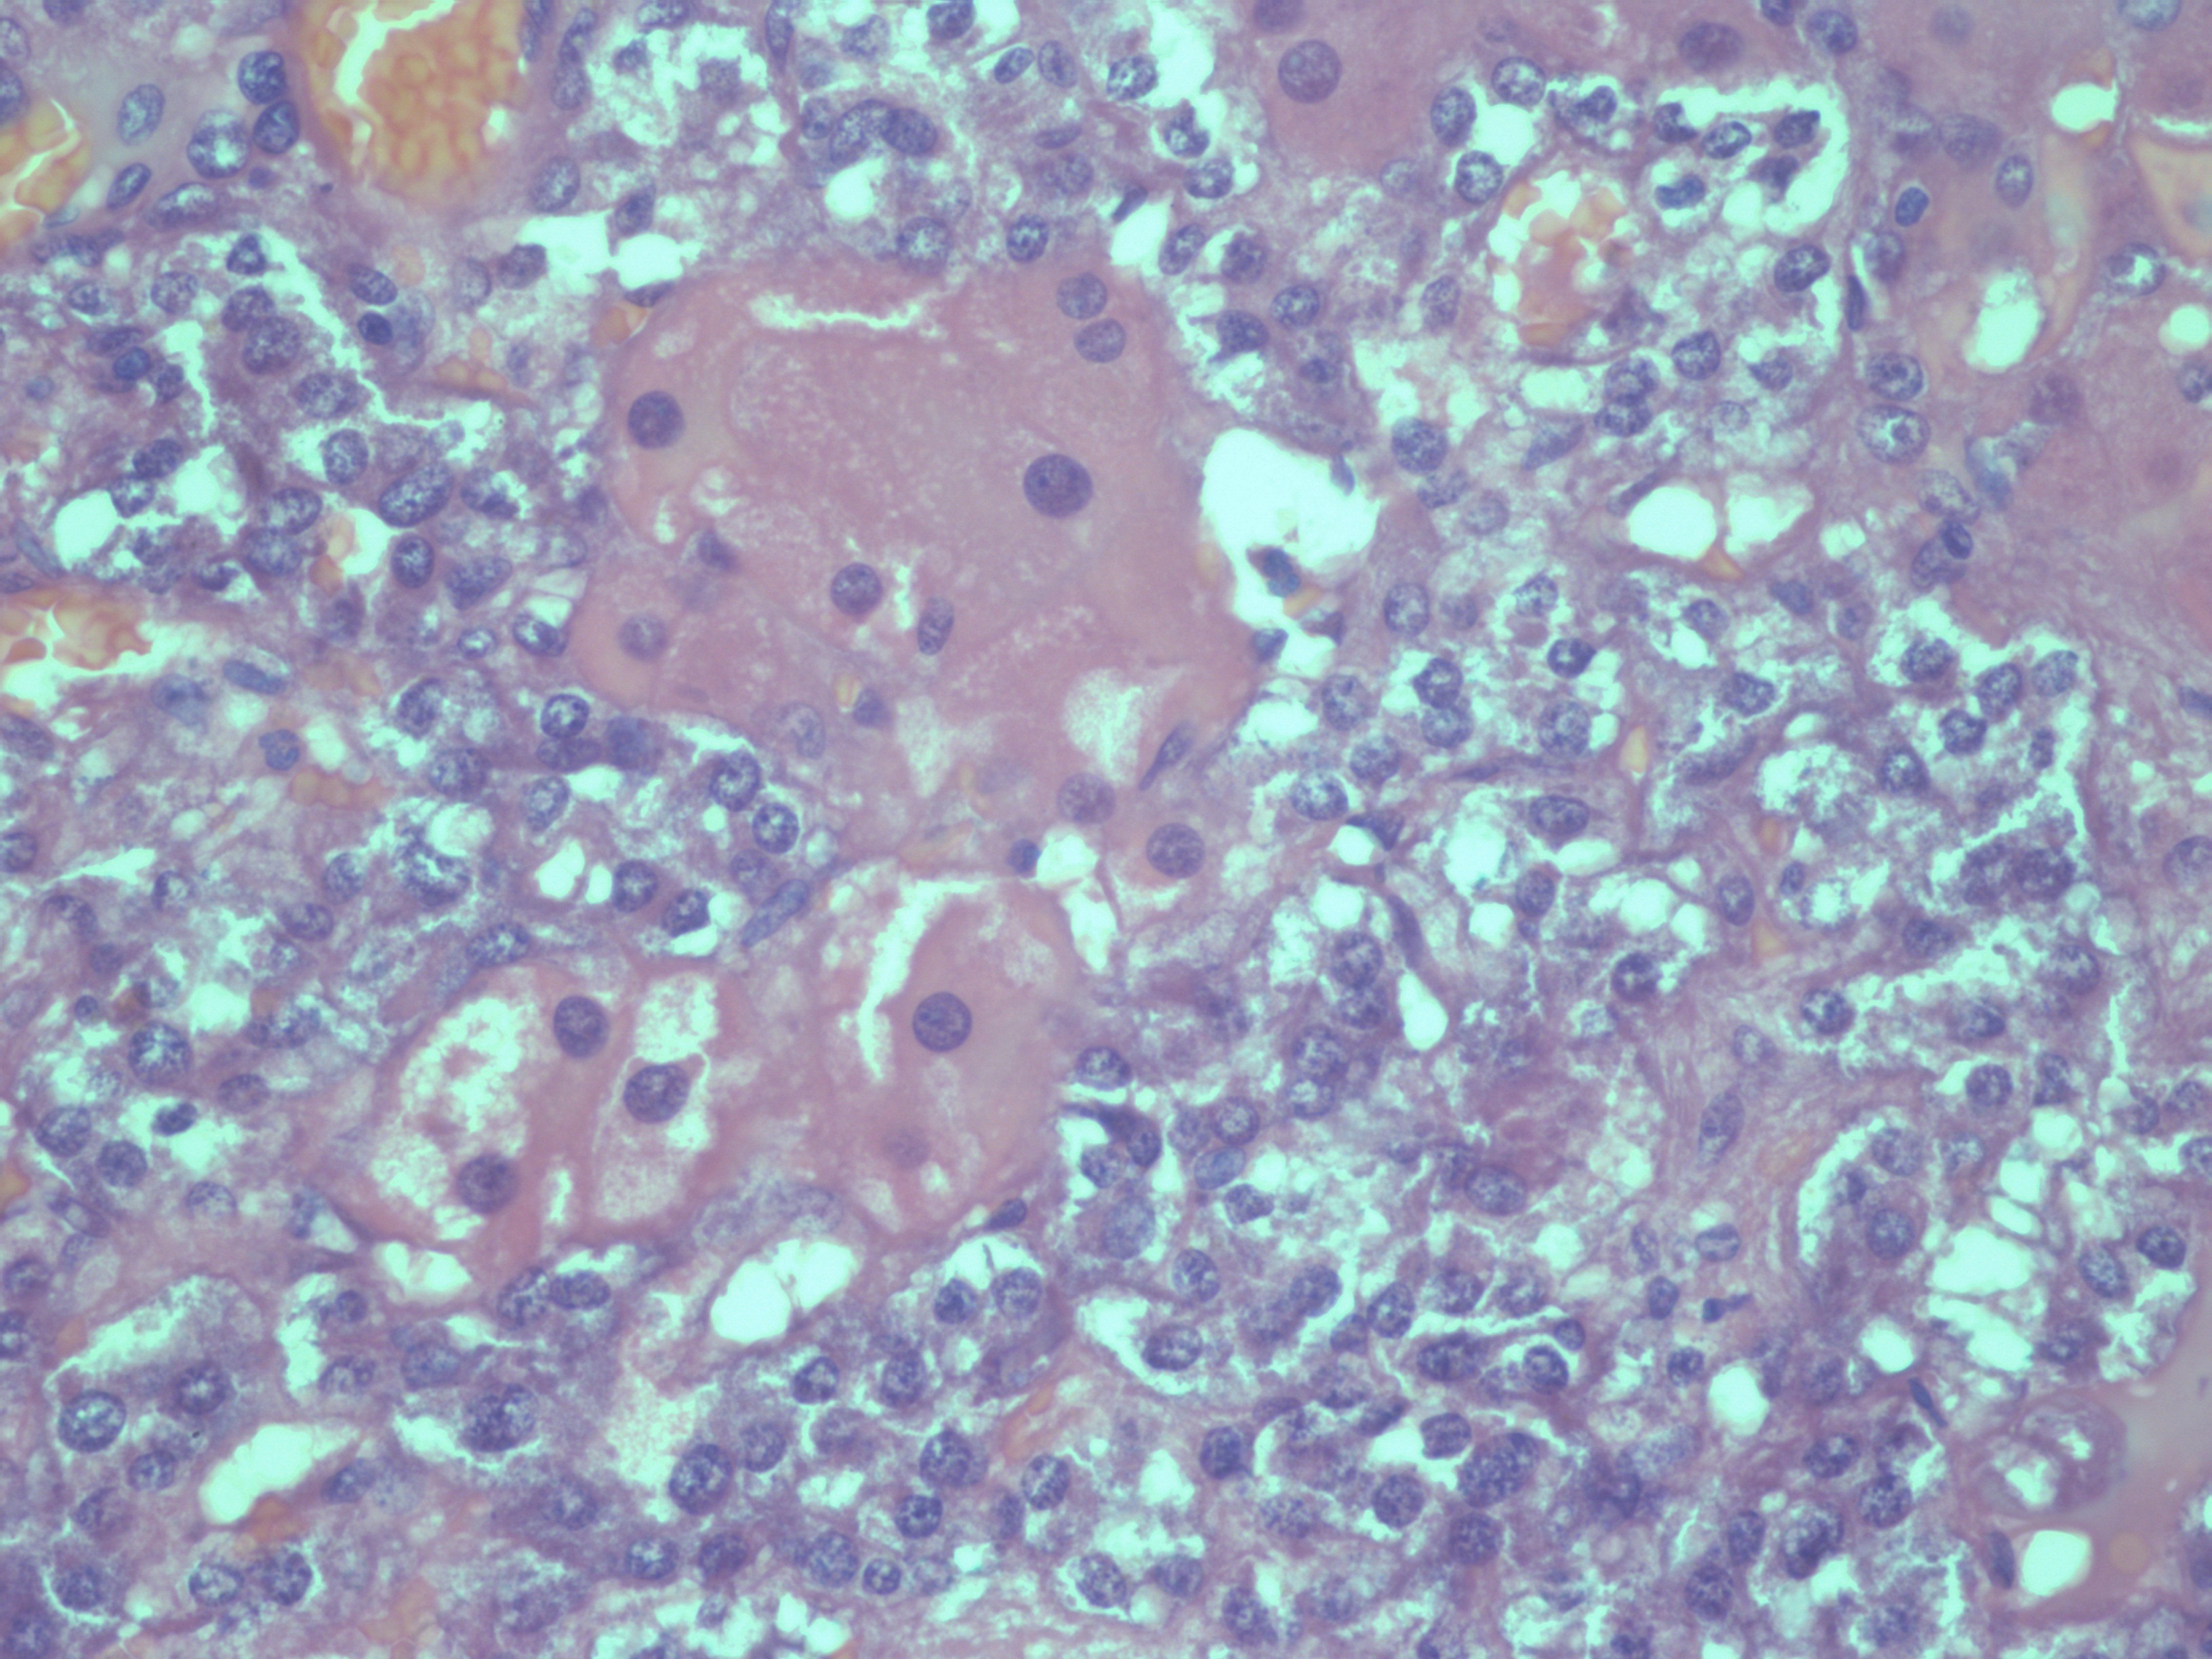

2. Смешанно-клеточное строение | |

| Тема | ||

| Тип | Исследовательские инструменты | |